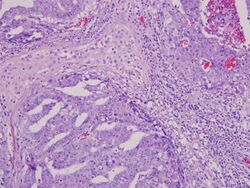

Micrograph (high magnification) of a seminoma. H&E stain.

Mixed germ cell tumor containing embryonal carcinoma, seminoma, and yolk sac tumor. The embryonal carcinoma component (upper left, upper right, and lower left) shows pseudoglandular growth with high-grade features of large, epithelioid, anaplastic cells with prominent nucleoli, indistinct cell borders with nuclear overlapping, pleomorphism, and frequent mitoses. The seminoma component (upper center) shows large, round-polyhedral cells with distinct cell membranes, abundant clear/watery cytoplasm, large central nuclei and prominent nucleoli. The yolk sac component (lower right, hugging the embryonal component) exhibits microcystic/reticular growth pattern.